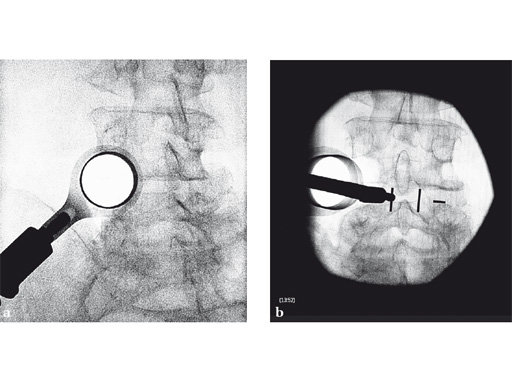

A 45-year-old woman who had failed nonoperative treatment underwent a minimally invasive decompression, facetectomy, discectomy, and interbody fusion via a right-sided approach through a 22 mm insight retractor. Subsequent instrumentation was performed through an ipsilateral miniopen and contralateral percutaneous approach (not shown).

Case provided by Roger Hrtl, New York, New York, USA